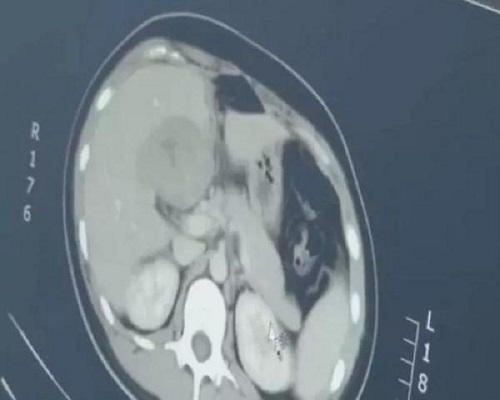

Hình ảnh màu xám bên trái là phôi thai, nằm gần gan. |

Theo đó, người phụ nữ này tên Long (29 tuổi) sống tại thị trấn Thiên Trường, Trừ Châu, tỉnh An Huy. Vào ngày 22/4, chị Long tới bệnh viện kiểm tra sau khi bị những cơn đau bụng hành hạ. Tại đây, chị Long cũng nói với các bác sĩ rằng chị đã mất kinh nguyệt trong 3 tháng và chị được chỉ định làm xét nghiệm máu.

Kết quả xét nghiệm máu cho thấy chị Long đã mang thai. Tuy nhiên, khi siêu âm, bác sĩ lại không tìm thấy bào thai nào trong tử cung nên yêu cầu chị Long đi chụp CT. Kết quả cho thấy có một khối lớn nằm ở gần gan và đó chính là bào thai.

Các bác sĩ cho biết hình thức mang thai này có thể gây chảy máu trong vì phôi thai đang phát triển gần mạch máu của gan và có thể dẫn đến tử vong. Vì vậy, chị Long đã đồng ý đình chỉ thai kỳ theo yêu cầu của bác sĩ.

Theo thư viện y khoa quốc gia Mỹ, mang thai ngoài tử cung ở gan là trường hợp cực kỳ hiếm gặp. Từ số liệu thống kê cho thấy trong vòng 35 năm trước tháng 11/1999, cả thế giới chỉ có 14 trường hợp được báo cáo.